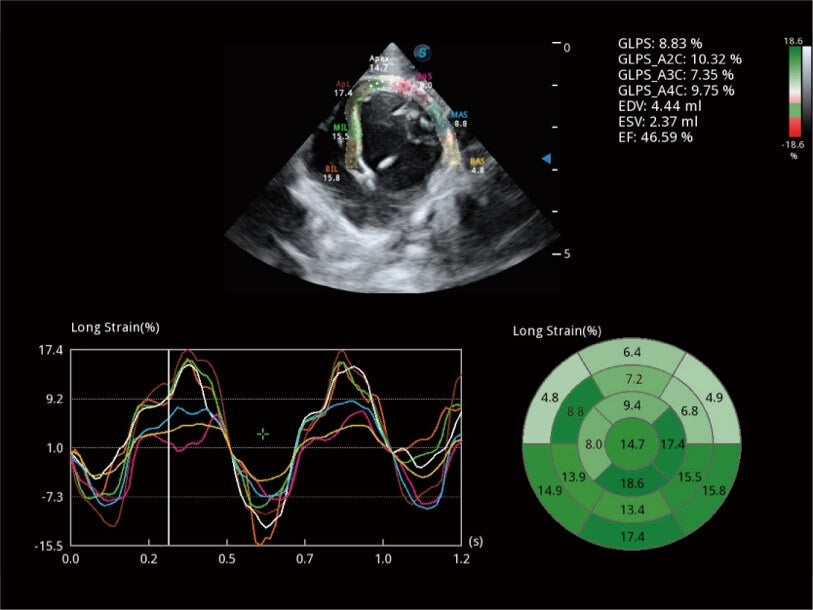

- Rendimiento superior: Imágenes excepcionales para abdomen, superficie y corazón.

- Herramientas cardíacas avanzadas: Evaluación completa de la función cardíaca.